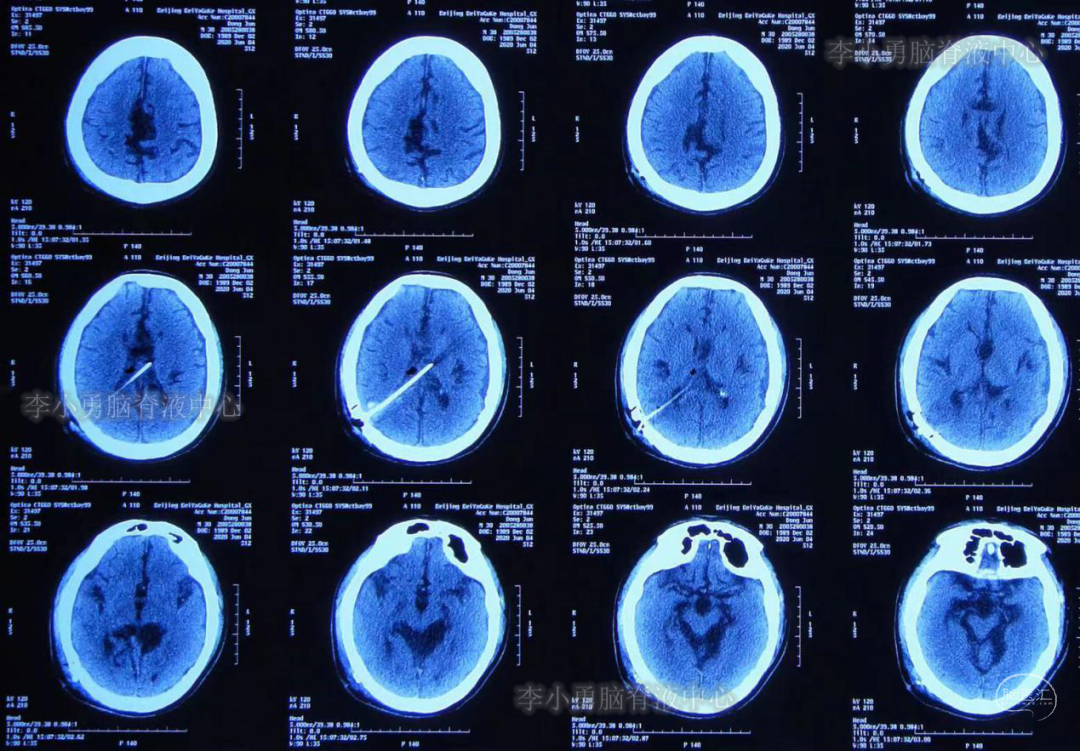

3年前(2017年,分流术后14年)患者再次出现头痛头晕,伴恶心呕吐。第3次就诊于山东省某三甲医院,行CT检查后(此片丢失),医生认为头部CT无异常,未进一步治疗,嘱患者回家观察。回家后患者头痛头晕仍间断出现,且出现越来越频繁,从开始的约半年出现一次头痛头晕到几乎每天都出现头痛头晕,且头痛程度越来越剧烈、无法忍受,于2020年5月11日(分流术后17年)第4次就诊于山东省某三甲医院住院,入院后行头部CT检查后,仍认为CT无异常(图-1)。

图-1:2020年5月12日头CT

给予患者行腰穿检查提示“颅压增高”,但具体“原因不详”,给予甘露醇降颅压治疗,但症状无好转。于2020年5月16日给予行头部MR检查:仍未见异常(图-2)。